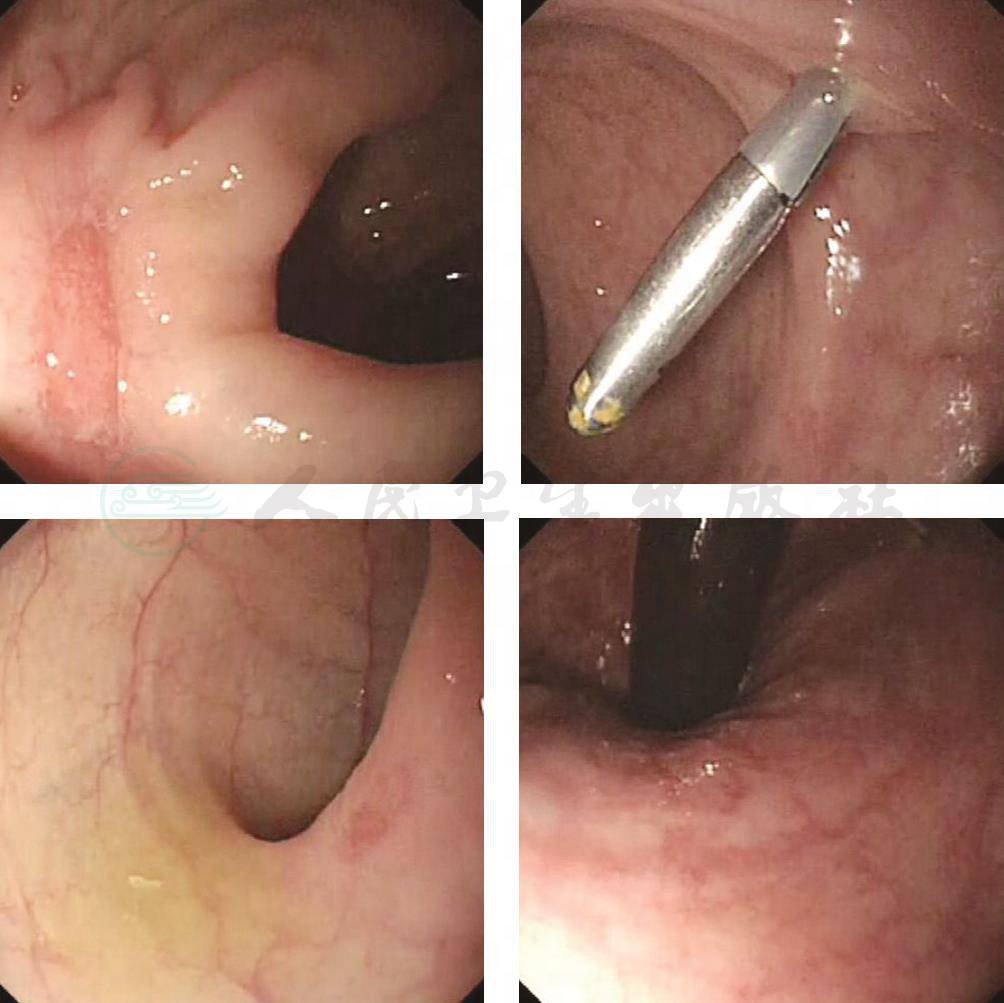

13.入院后病情变化 患者入院1周后头痛无好转,仍有发热,最高39.3℃,同时出现口腔溃疡、肛周溃疡,突发解鲜血便,伴血块,量约1 000ml,急诊肠镜及镜下止血。止血后复查肠镜(图2):进镜至回肠末段未见异常,回盲瓣呈唇形,舒缩正常。盲肠、升结肠、肝曲、横结肠脾曲、降结肠、乙状结肠、直肠黏膜充血水肿,血管纹理紊乱,全结肠可见散发大小不一溃疡愈合期改变,可见红色肉芽,较大者0.8cm×0.4cm,直肠可见一钛夹。结论:结肠多发溃疡,直肠溃疡出血治疗术后改变。

图2 肠镜